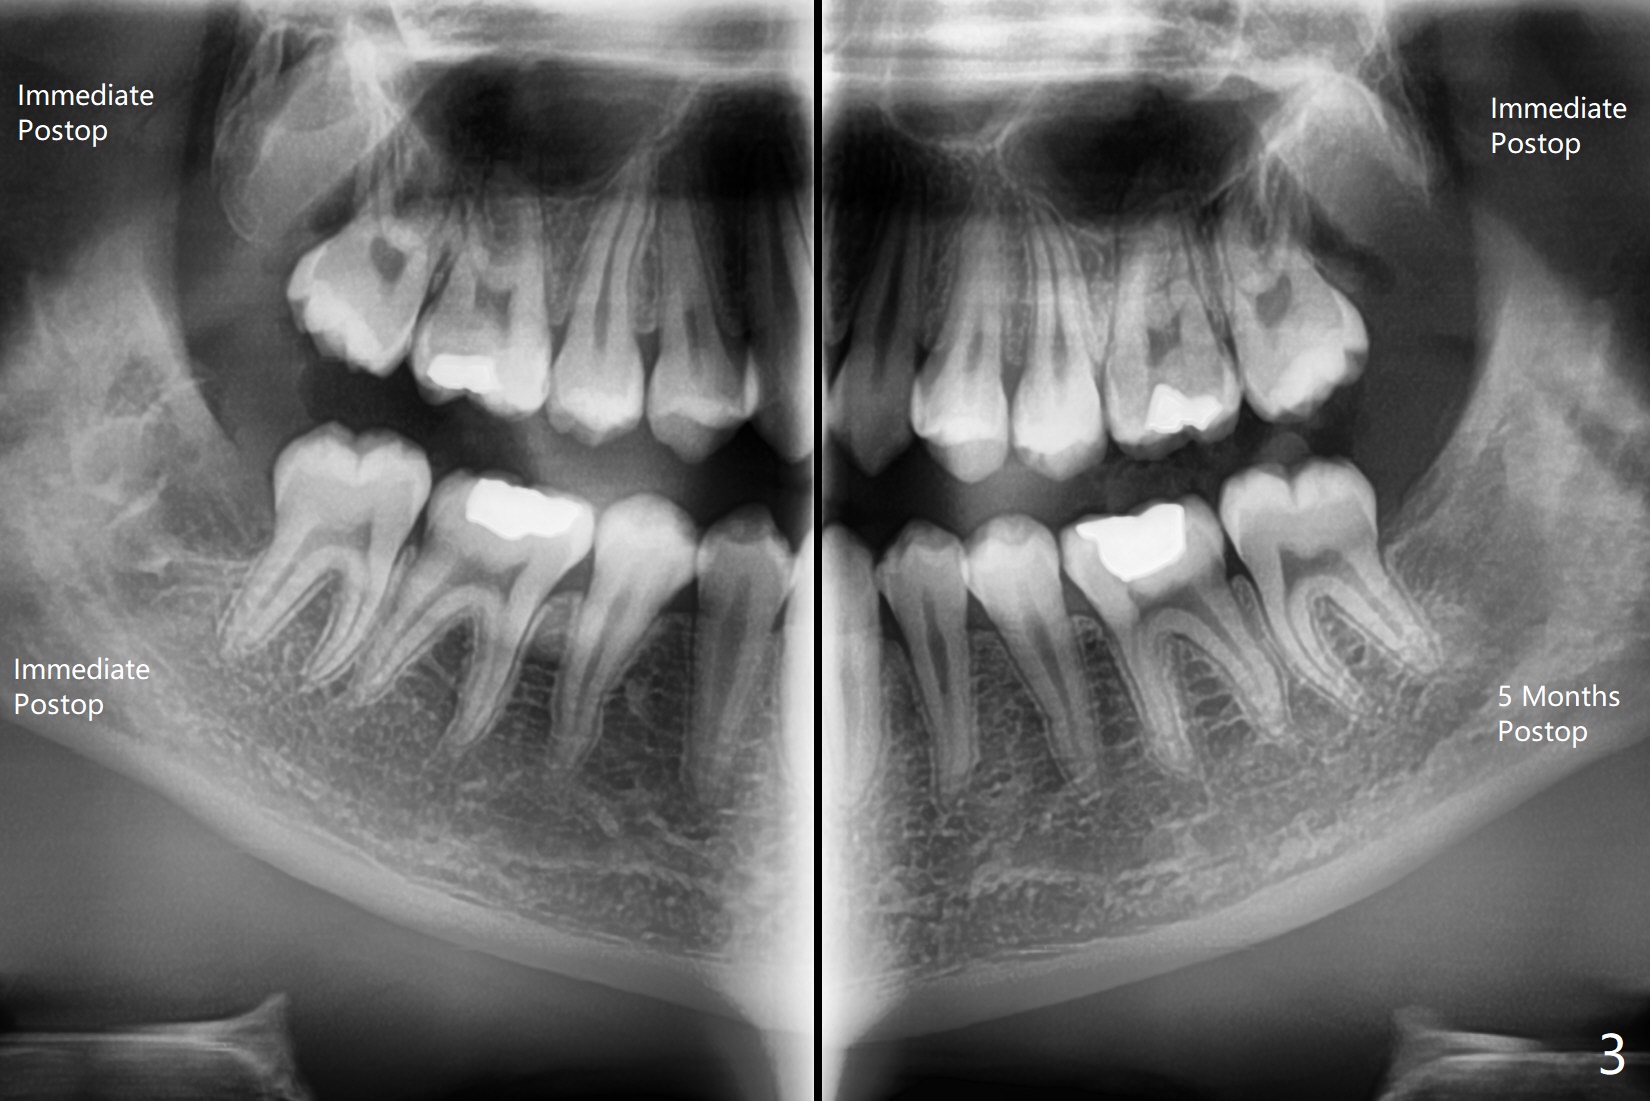

左下智齿疼痛(图一),截骨后牙齿容易松动,然后切断两次,顺利拔除,放置Osteogen Plug,4-0 铬羊肠线缝合(图二)。5个月后另外三个智齿拔除(右下放置胶原塞;上智齿拔除盲目,困难,稍微早些),左下智齿牙槽窝愈合(图三);近中牙槽嵴重建。